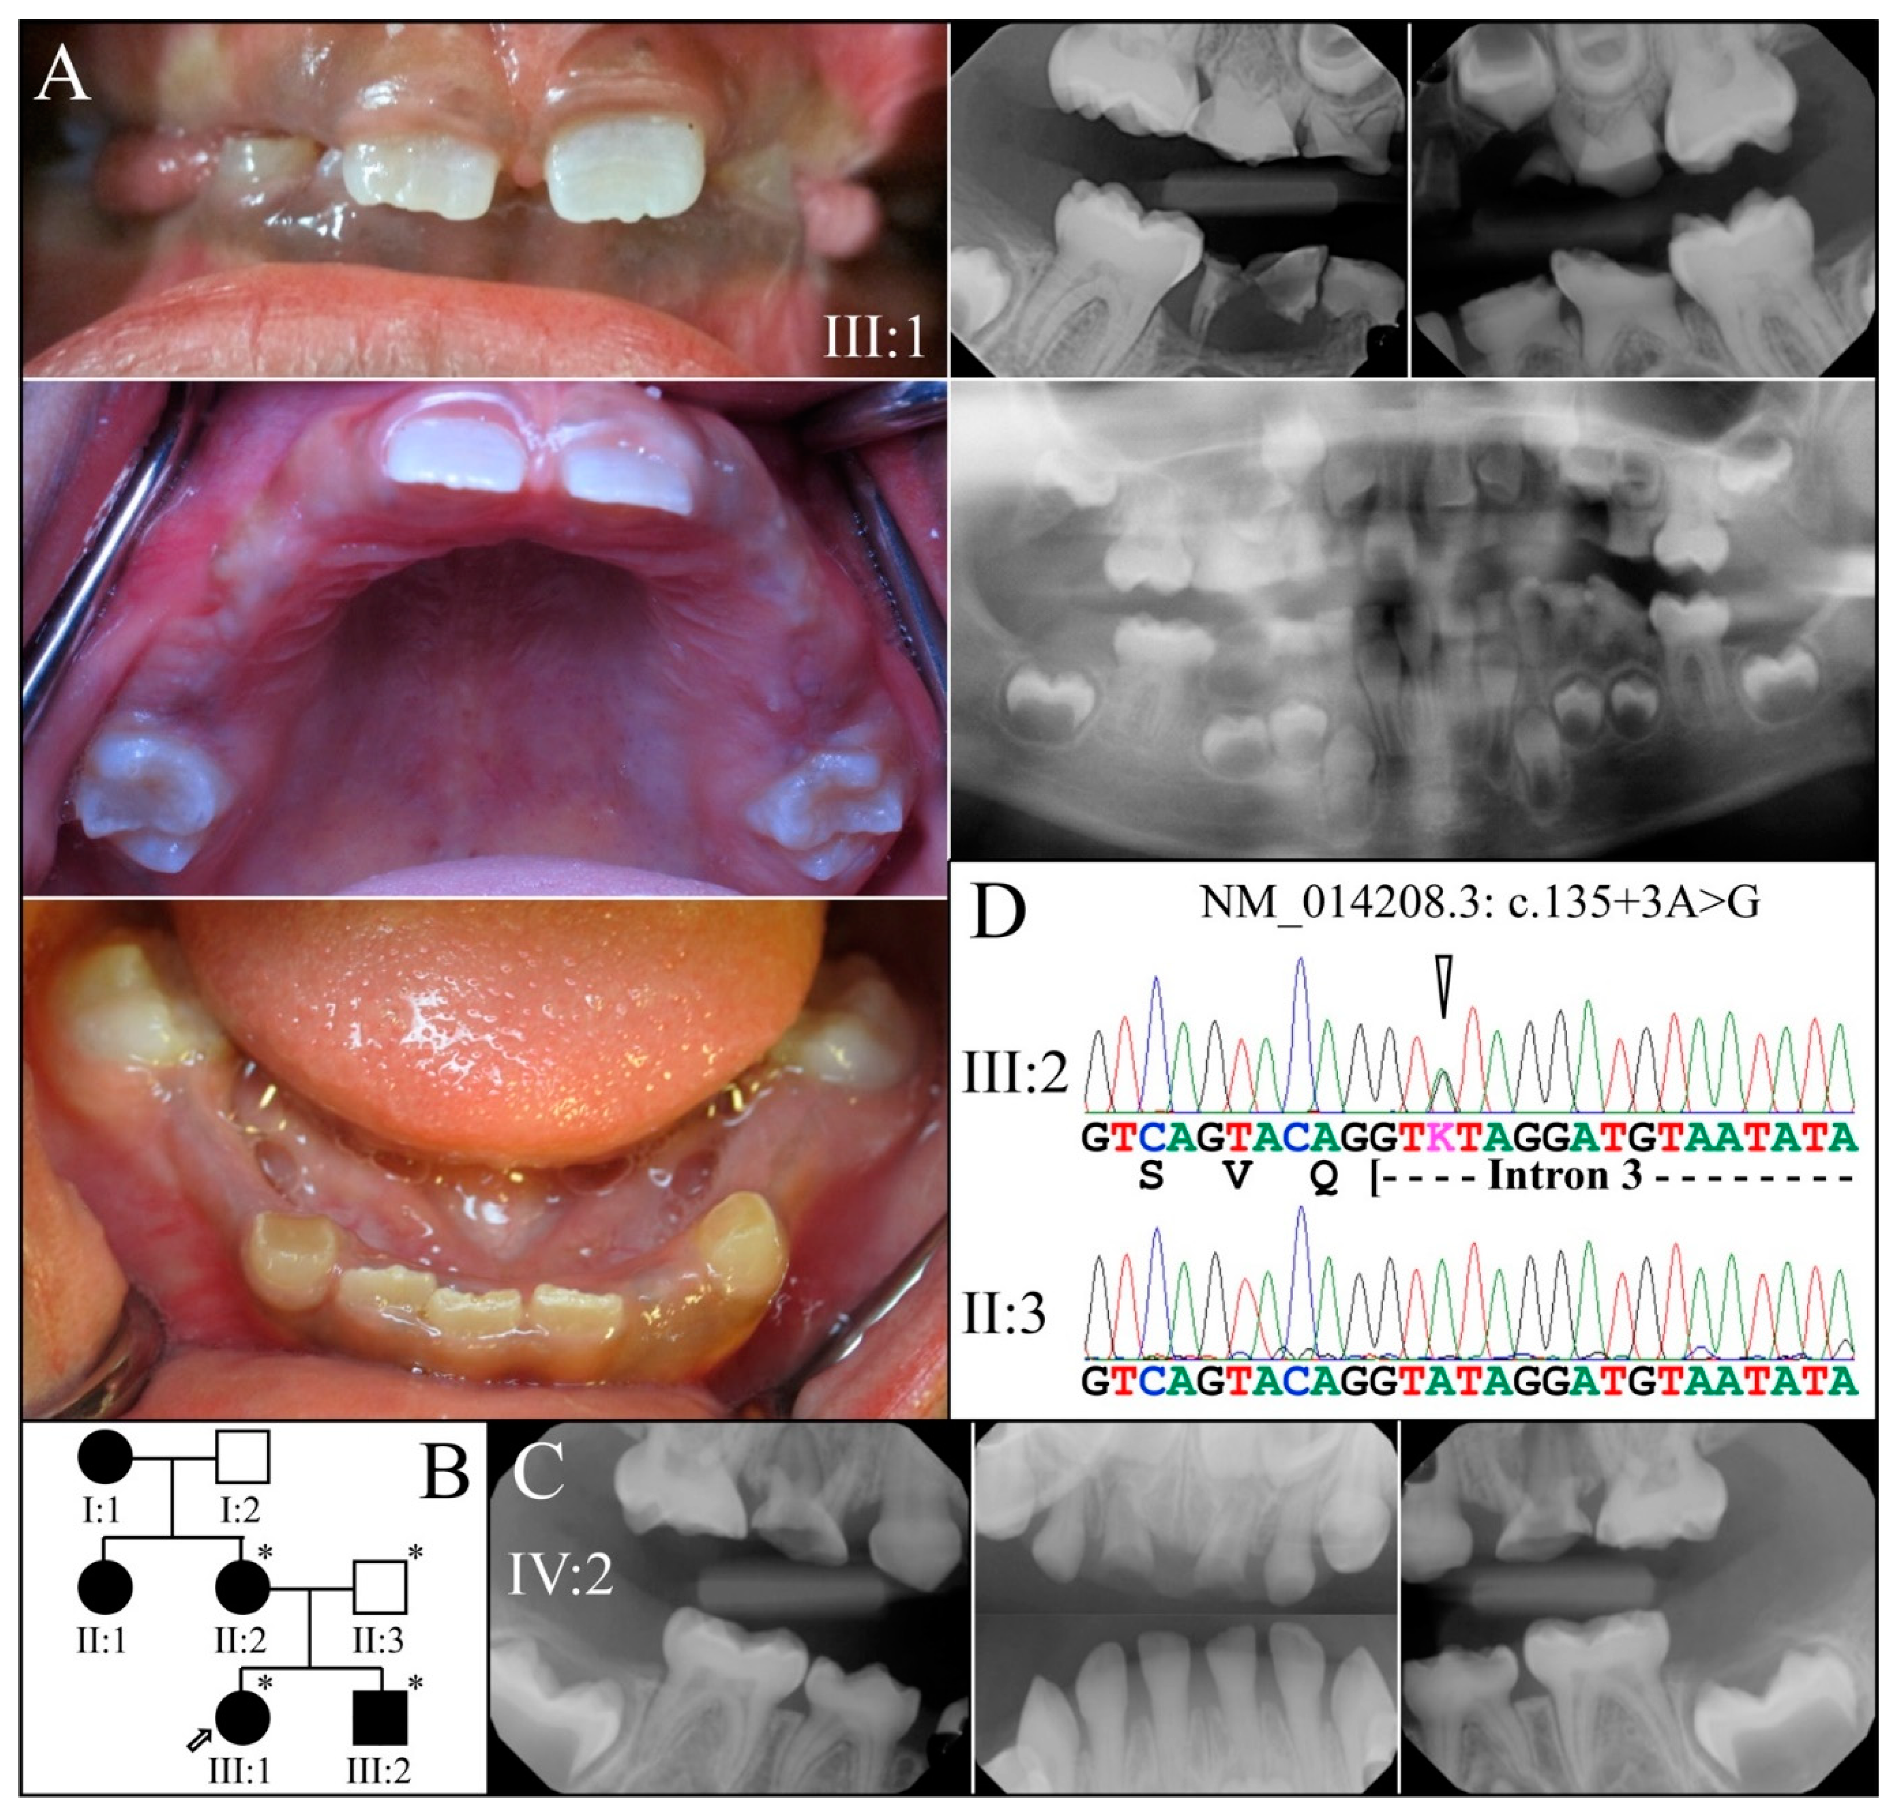

3.2. Four Families with DGI-III: 5′ DSPP Mutations

| 21 | Intron 3 | g.8663A>G | c.135+3A>G | p.(?) | Family 4 [78] |

| 4 | Sanger Sequencing | NG_011595.1:g.8663A>G; NM_014208.3:c.135+3A>G | Splice Donor | |